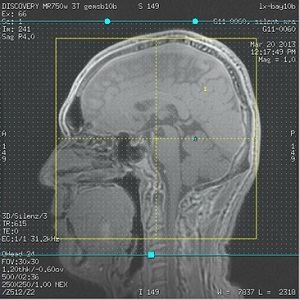

Figure 1. Example of IR saturation band placement

- The position of ASL tagging plane is determined by the inferior boundary of the IR band.

- The position of ASL control plane is determined by the superior boundary of the IR band.

- Adjust the IR band so that superior/inferior edges are outside the 3D slab.

Placement of the IR band edges is critical in order to avoid signal suppression in the final images.